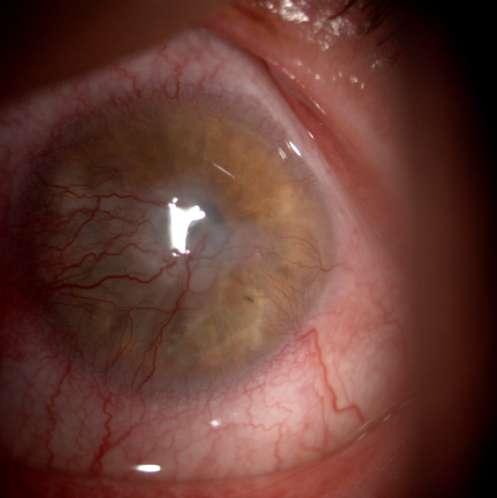

Caso aportado por Dr. Nathan Dukes

ü Hombre 39 años con antecedentes de Axenfeld Rieger y glaucoma asociado acude a control en Hospital del Salvador.

ü Hipoplasia estromal del iris - Policoria

ü Embriotoxon posterior

ü Tubo de Válvula de ahmed

ü Ectopia pupilar

ü Adherencia irido corneales

ü El síndrome de Axenfeld-Rieger (SAR) es una entidad rara, autosómica dominante, que se caracteriza por una penetrancia completa y expresividad variable.

ü Los defectos oculares clásicos del síndrome de Axenfeld-Rieger incluyen hipoplasia del iris, adherencias iridocorneales, corectopia, policoria, embriotoxon posterior, y otros rasgos menos frecuentes como cataratas, desprendimiento de retina y microcórnea.

ü Aproximadamente la mitad de los individuos afectados desarrollan glaucoma.

ü Las anomalías sistémicas asociadas incluyen las malformaciones faciales (telecantus, hipoplasia del maxilar), anomalías dentarias y piel periumbilical redundante entre otras.

Shields MB, Buckley E, Klintworth GK & Thresher R. Axenfeld-Rieger syndrome. A spectrum of developmental disorders. Surv Ophthalmol. Mayo-Junio, 1985; 29(6):387-409